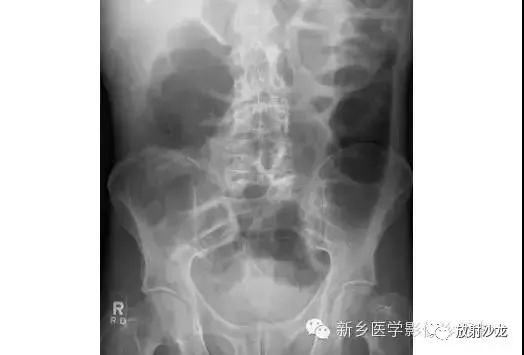

病例二:

上图腹部平片检查是一6岁男孩,出现呕吐和急性右髂窝疼痛进行的。两个关键的发现在哪里?(提示:通过放射科医生所提供的箭头可以缩小关注点。)

右髂窝多个扩张的小肠襻出现小的钙化结节。小肠袢可与大肠区分开来,因为小肠的环状襞延伸至整个肠壁,而结肠袋只是部分延伸存在。在右下腹(箭头)的钙化结节高度提示阑尾粘连。这个病人开腹手术发现阑尾粘连致小肠梗阻。